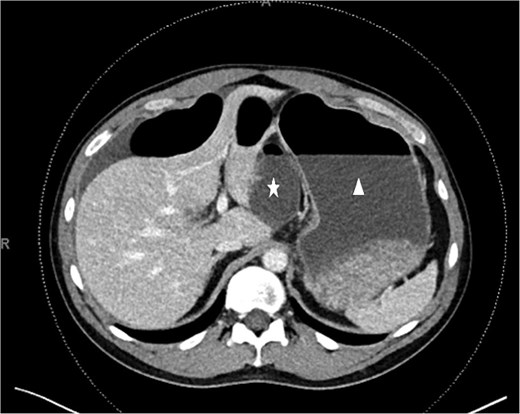

On examination, he was vitally stable. His abdomen was soft, distended, with generalized tenderness. Laboratory investigations were unremarkable except for an elevated white blood cell count of 14. An abdominal computed tomography (CT) scan revealed findings suggestive of a closed-loop small-bowel obstruction, with presumed internal herniation through the foramen of Winslow (Fig. 1).

CT scan. Unusual dilated and fluid-filled small bowel (white star) behind the distended stomach (white triangle).